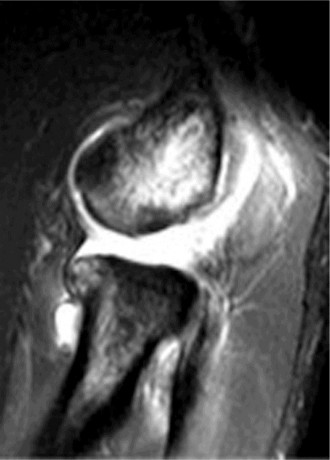

Magnetic Resonance Imaging (MRI)

An MRI of the elbow was obtained to assess the integrity of the lateral collateral ligament (LCL) complex and rule out any other soft tissue pathology. The MRI sequences (T1, T2, PD Fat Sat) clearly demonstrated a full-thickness tear of the lateral ulnar collateral ligament (LUCL) at its humeral attachment, with retraction and edema. The common extensor origin appeared intact, although some surrounding signal change suggested chronic inflammation. No significant osteochondral defects of the capitellum or radial head were identified. The medial collateral ligament (MCL) complex appeared intact. The biceps and triceps tendons were unremarkable. No loose bodies were seen. The posterolateral capsule also showed signs of laxity and attenuation.